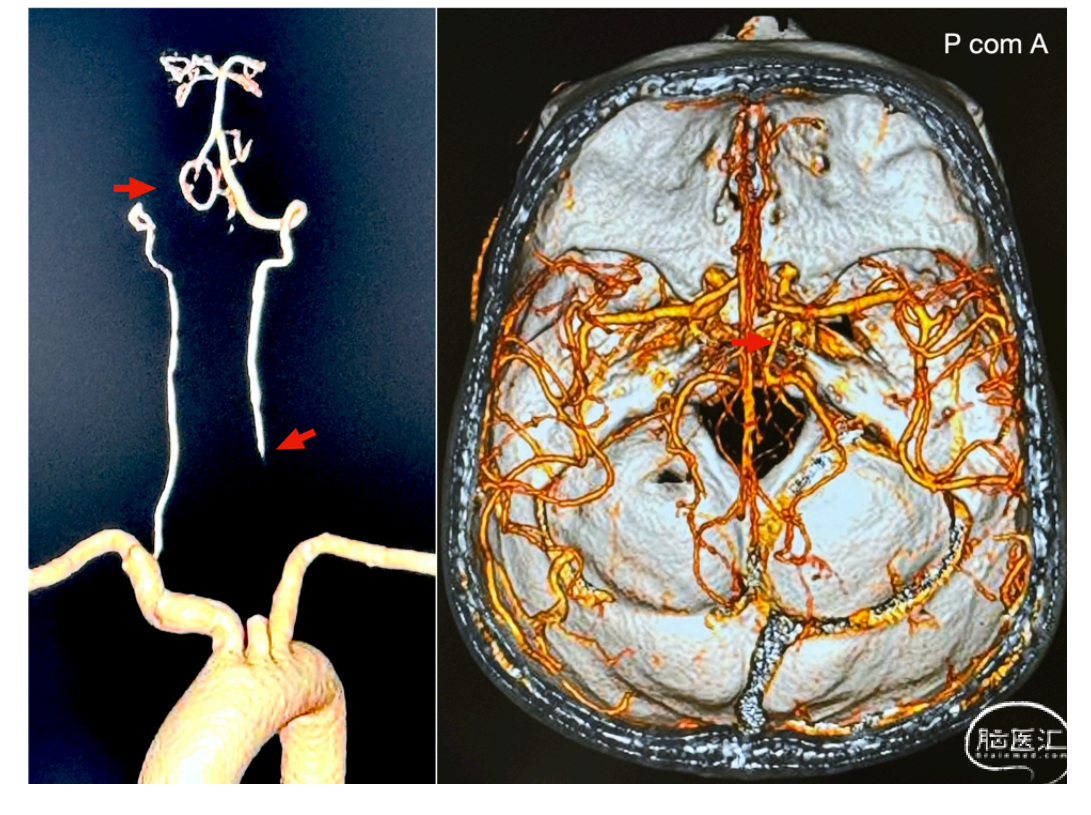

本期脑医汇为大家分享:天津市环湖医院【佟小光教授】的精彩病例内容:颈横动脉-椎动脉吻合治疗双侧椎动脉闭塞,欢迎阅读和分享!病例视频观看点击图片观看视频讲者:佟小光讲题:颈横动脉-椎动脉吻合治疗双侧椎动脉闭塞病例内容截图声明:脑医汇旗下神外资讯、神介资讯、神内资讯、脑医咨询、Ai Brain 所发表内容之知识产权为脑医汇及主办方、原作者等相关权利人所有。投稿邮箱:NAOYIHUI@163.com 未经许可,禁止进行转载、摘编、复制、裁切、录制等。经许可授权使用,亦须注明来源。欢迎转发、分享。